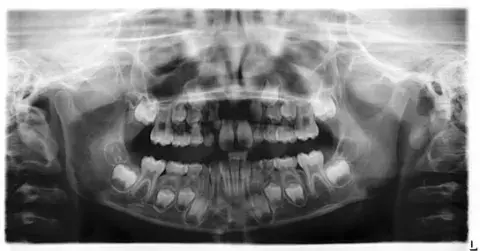

Orthopantomogram (OPG)